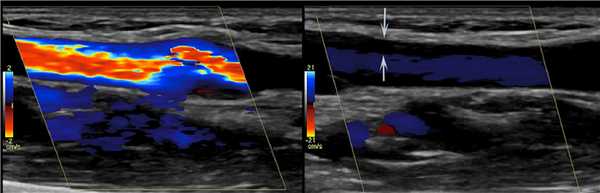

ЦДК — эффективный вспомогательный методом для подтверждения проходимости вены.

Весь широкий просвет вены должен полностью обозначатся цветом.

Во время сканирования ЦДК в крупных центральных венах физиологическое колебание направления кровотока.

Из-за сокращения правого предсердия а-волна возвращается в венозное русло — реверсный тип кровотока.

Рисунок. При ЦДК ВЯВ полностью закрашена, что исключает тромбоз.

Элайзинг эффект появляется, когда цветовая шкала не соответствует скорости кровотока в венах.

При в сосуде с большей скоростью кровотока, часто не видно медленный ламинарного потока вдоль стенки.

Можно неправильно трактовать; возможно перепутать этот артефакт со сгустком, прикрепленным к стенке.

Рисунок. Когда цветовая шкала настроена на более высокий диапазон скорости, цвет заполняет только центральный сегмент с высокой скоростью тока крови. Зона вдоль стенок это артефакт, не стоит путать с пристеночным тромбом.